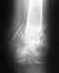

Здравствуйте, мне 30 лет, в сентябре 2015 года попал в ДТП. В местной больнице была проведена операция остеосинтез левой бедренной кости.

Операция прошла не совсем удачно - не смогли до конца закрутить один из нижних болтов, сорвали резьбу. Врач сказал через год всю конструкцию необходимо снимать. Беспокоят вопросы: можно ли удалить такую конструкцию и снова ходить на своих ногах? Будут ли чем-то заполнять отверстие от бедренного проксимального болта? Где лучше сделать такую операцию? Снимки прилагаю к сообщению.